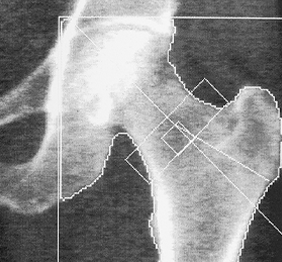

DEXA (osteodensitometrie)

Este o metoda moderna, precisa si complet nedureroasa prin care poti afla daca oasele tale sunt puternice sau daca exista risc de osteoporoza.